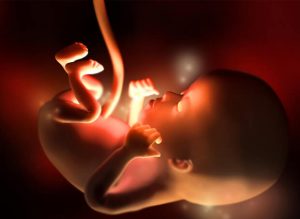

Na 12ª semana da gravidez, a atividade do feto se torna mais intensa e seus órgãos começam a tomar forma, se fixar nos seus lugares e inclusive a funcionar.

Nessa semana, a última do primeiro trimestre, seu bebê chega a medir ente 5 e 6 centímetros e pesar entre 8 e 14 gramas. Seu coração bate muito forte, aproximadamente 160 pulsações por minuto e seus movimentos começam a se multiplicar, ainda que sejam imperceptíveis para você.

O tamanho de seu bebê é igual ao de uma ameixa a esta altura da gestação. De fato, entre a última semana e esta, ele cresceu aproximadamente 15%. Suas extremidades já estão formadas, os órgãos começam a amadurecer rapidamente e inclusive seus intestinos, até agora conectados a base do cordão umbilical, se deslocam da cavidade abdominal.

Sua cabeça já adquiriu sua forma arredondada. Sua boca já pode se abrir e fechar e as orelhas já estão no lugar correto. As unhas começam a se definir, assim como as cordas vocais. Durante a 12ª semana da gravidez, os rins começam a gerar pequenas quantidades de urina e inclusive aparecem os primeiros vestígios de pelos no corpo.

Porém, ainda não se pode distinguir o sexo do bebê através da ecografia, o aparato genital está em pleno desenvolvimento nesta etapa. A essa altura, além disso, o bebê já é capaz de bocejar, soluçar e engolir. É aqui quando verdadeiramente as maravilhas da natureza começam a ocorrer nas nossa frente ao ver o que nosso filho, que está a caminho, já é capaz de fazer.